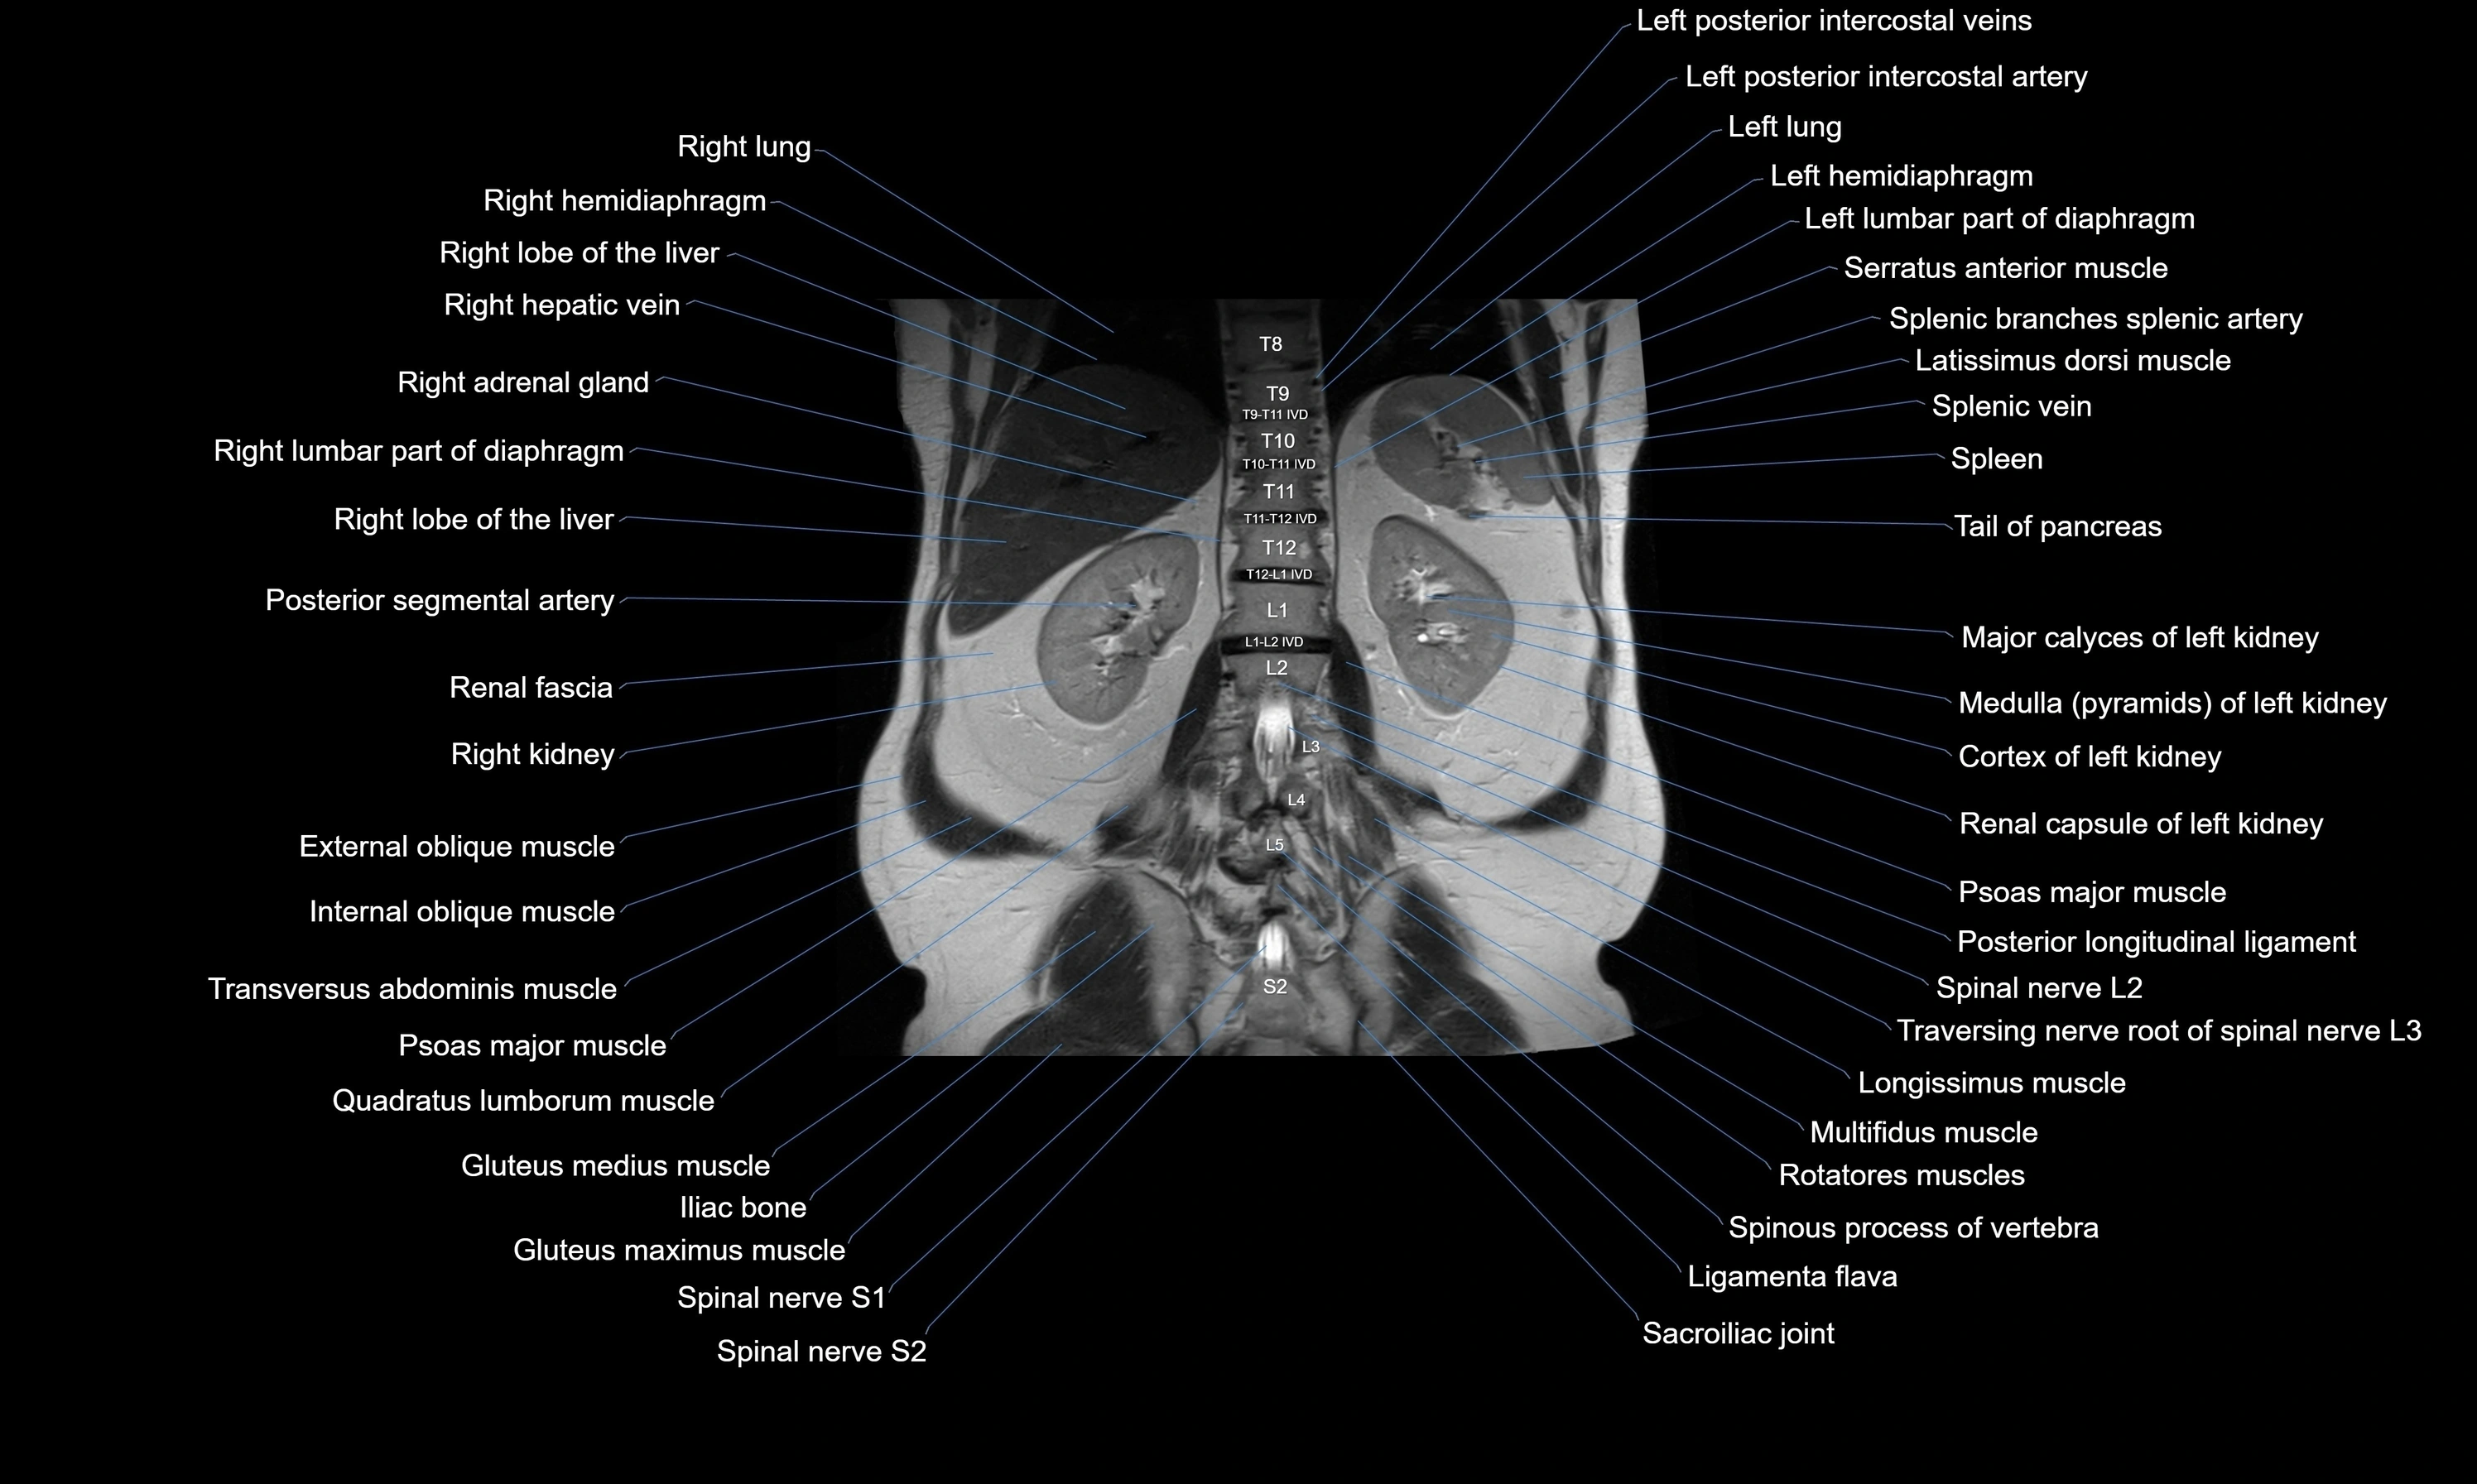

MRI images